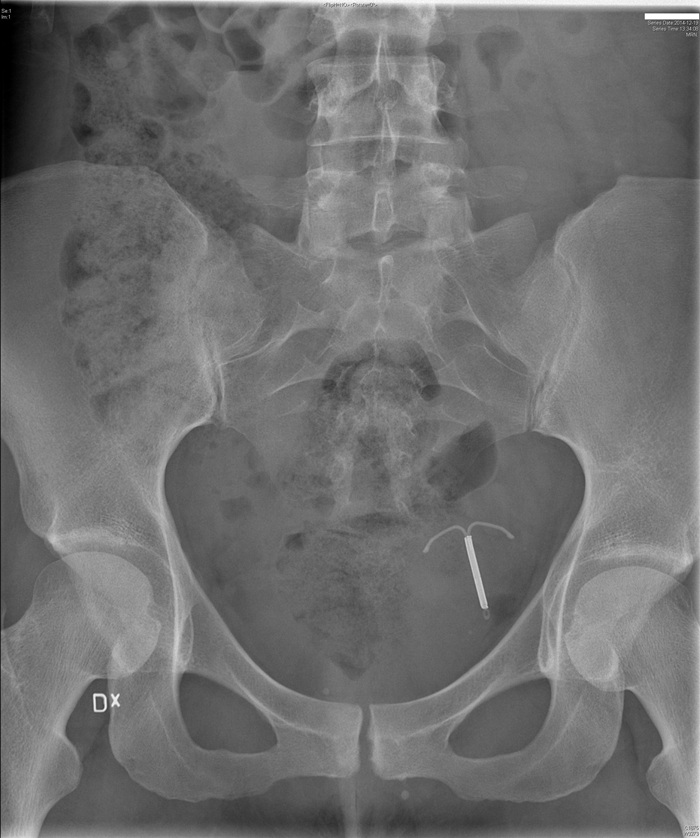

Ακτινογραφία με σπιράλ που διαπέρασε την μήτρα και εντοπίζεται στην πύελο

Οι κίνδυνοι που σχετίζονται με οποιονδήποτε από τους δύο τύπους σπιράλ περιλαμβάνουν:

- Διάτρηση (τρύπημα ή διείσδυση) του σπιράλ στην μήτρα ή σε ένα κοντινό όργανο η οποία μπορεί να προκαλέσει σοβαρή αιμορραγία.

Αυτές οι παρενέργειες είναι σπάνιες, αλλά μια μελέτη που χρηματοδοτήθηκε από τον FDA και δημοσιεύτηκε στο Lancet το 2022 κατέληξε ότι η διάτρηση ήταν πολύ πιο πιθανό να συμβεί από ό,τι είχε υποτεθεί προηγουμένως. Οι κίνδυνοι ήταν υψηλότεροι για τις γυναίκες που είχαν τοποθετήσει σπιράλ τους πρώτους μήνες μετά τον τοκετό.